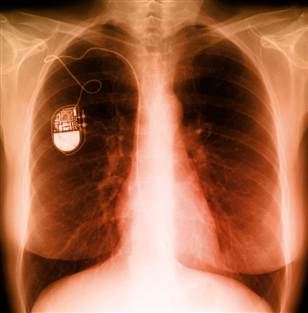

Кардиостимулятор - это маленькое устройство, размером с карманные часы, которое устанавливают под кожу, возле сердца, для контроля над сердечным ритмом. Он может быть необходим по целому ряду причин, главным образом, из-за аритмии. Кардиостимулятор могут имплантировать временно, например, при замедленном сердцебиении после сердечного приступа, хирургической операции или передозировки лекарственных средств. Постоянная имплантация кардиостимулятора может быть необходима […]